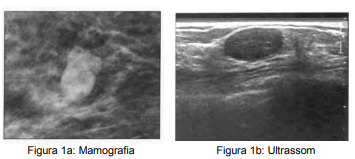

A.J.A.C. 42 anos, feminino, procura mastologista devido à alteração em exame mamográfico de rastreio BI-RADS® 0 (imagem 1a). Realiza complementação diagnóstica com ultrassonografia de mamas que apresentou o seguinte achado (imagem 1b). Ao exame físico, paciente não possui qualquer alteração em mamas. De acordo com os achados da imagem, assinale a alternativa correta que apresenta a classificação do BI-RADS® ultrassonográfico e conduta adequada.